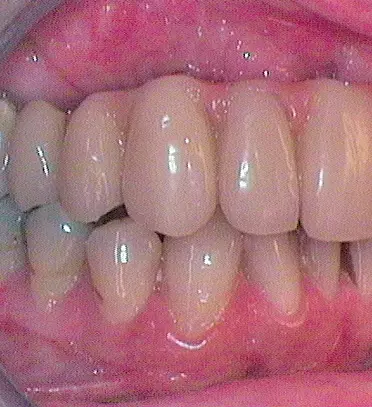

Nach Freilegung der Implantate regio 026,027 im Februar 2020, bei der auch die Implantation regio 037 (T3, Zimmer Biomet Dental, 4,0 mm x 13,0 mm) vorgenommen wurde (Abb. 32 OPG nach Freilegung), erfolgte im März nach Abformung mit offenem Löffel (open tray technique) und Gesichtsbogenregistrat die prothetische Versorgung mittels CAD/CAM gefräster Abutments (Dentaltechnik Hessel und Lutgen, Trier) und transversal verschraubter, verblockter VMK-Kronen (Abb. 33-36). Die Freilegung und Versorgung des Implantates 037 ist zusammen mit der Entfernung des Zahnes 38 für Juli 2020 geplant.